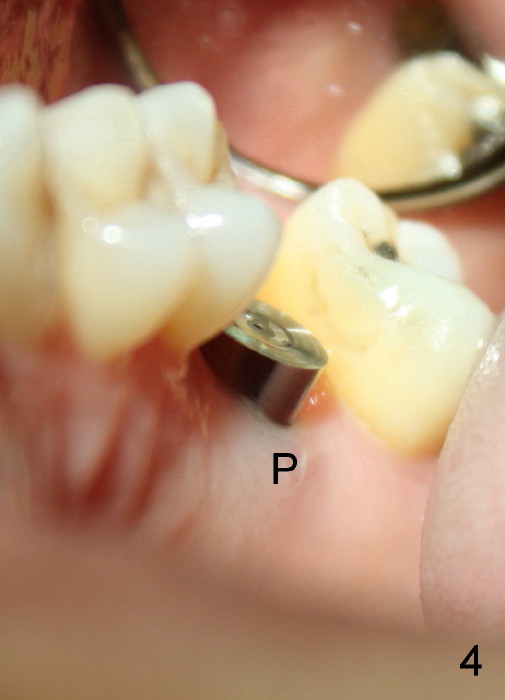

Prior to placement of 6x17 mm soft tissue level implant (Fig.1), the same size of tap is used. When the latter is removed, there is a small defect in the buccal wall of the osteotomy (mainly in the palatal socket) with the intact sinus membrane. There is no intraop or postop nasal hemorrhage. The patient returns for restoration 7 months postop; it appears that there is osteo-integration (Fig.2 with the mesial gap getting smaller (>)). The gingiva is healthy buccal (Fig.3: B) and palatal (Fig.4: P). The mesial gap is closed with formation of dense bone 4 years post cementation (Fig.7). Fig.5 is the preop PA of the patient, which shows that the palatal root (pink dashed line) is above the sinus floor and surrounded by the lamina dura. Fig.6 is a coronal section of the 2nd molar of another patient, which shows that the palatal root is 5-6 mm above the sinus floor. Upper Molar Immediate Implant Follow-Up Xin Wei, DDS, PhD, MS 1st edition 10/13/2013, last revision 05/18/2018